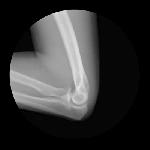

JOINTS IN MOTION

Cameron Drake of San Francisco has created a collection of magnificent images showing joints in motion. He was aided by orthopedic physician Dr. Noah Weiss and the finished product is completely amazing. If you’d like to know more about the project, please check out Drake’s blog.